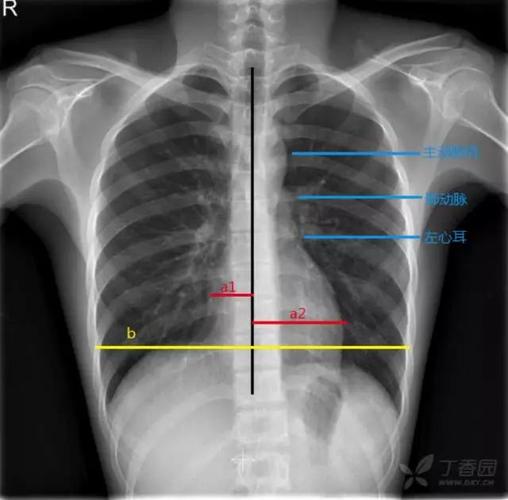

6步法从胸片进行胸部评估

来,我教你看胸片!

胸片怎么看